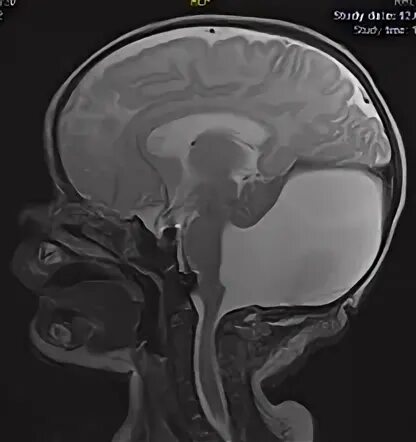

Денди уокера мрт